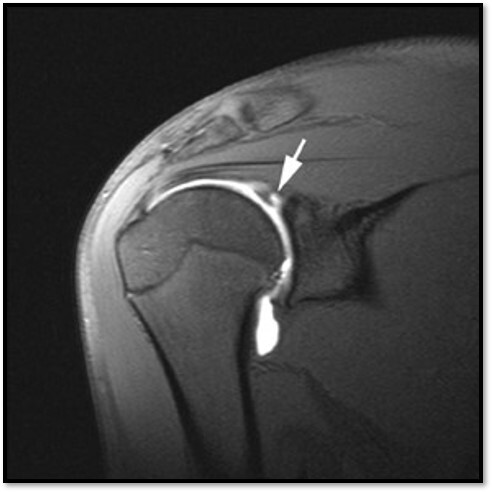

What is this showing?

MR Shoulder with Contrast

What is an example of a pathology that requires MRI contrast?

A Labral tear in the shoulder

What contrast must be given for pathologies that cannot be seen on MRI without it?

Iodinated contrast and gadolinium mixed